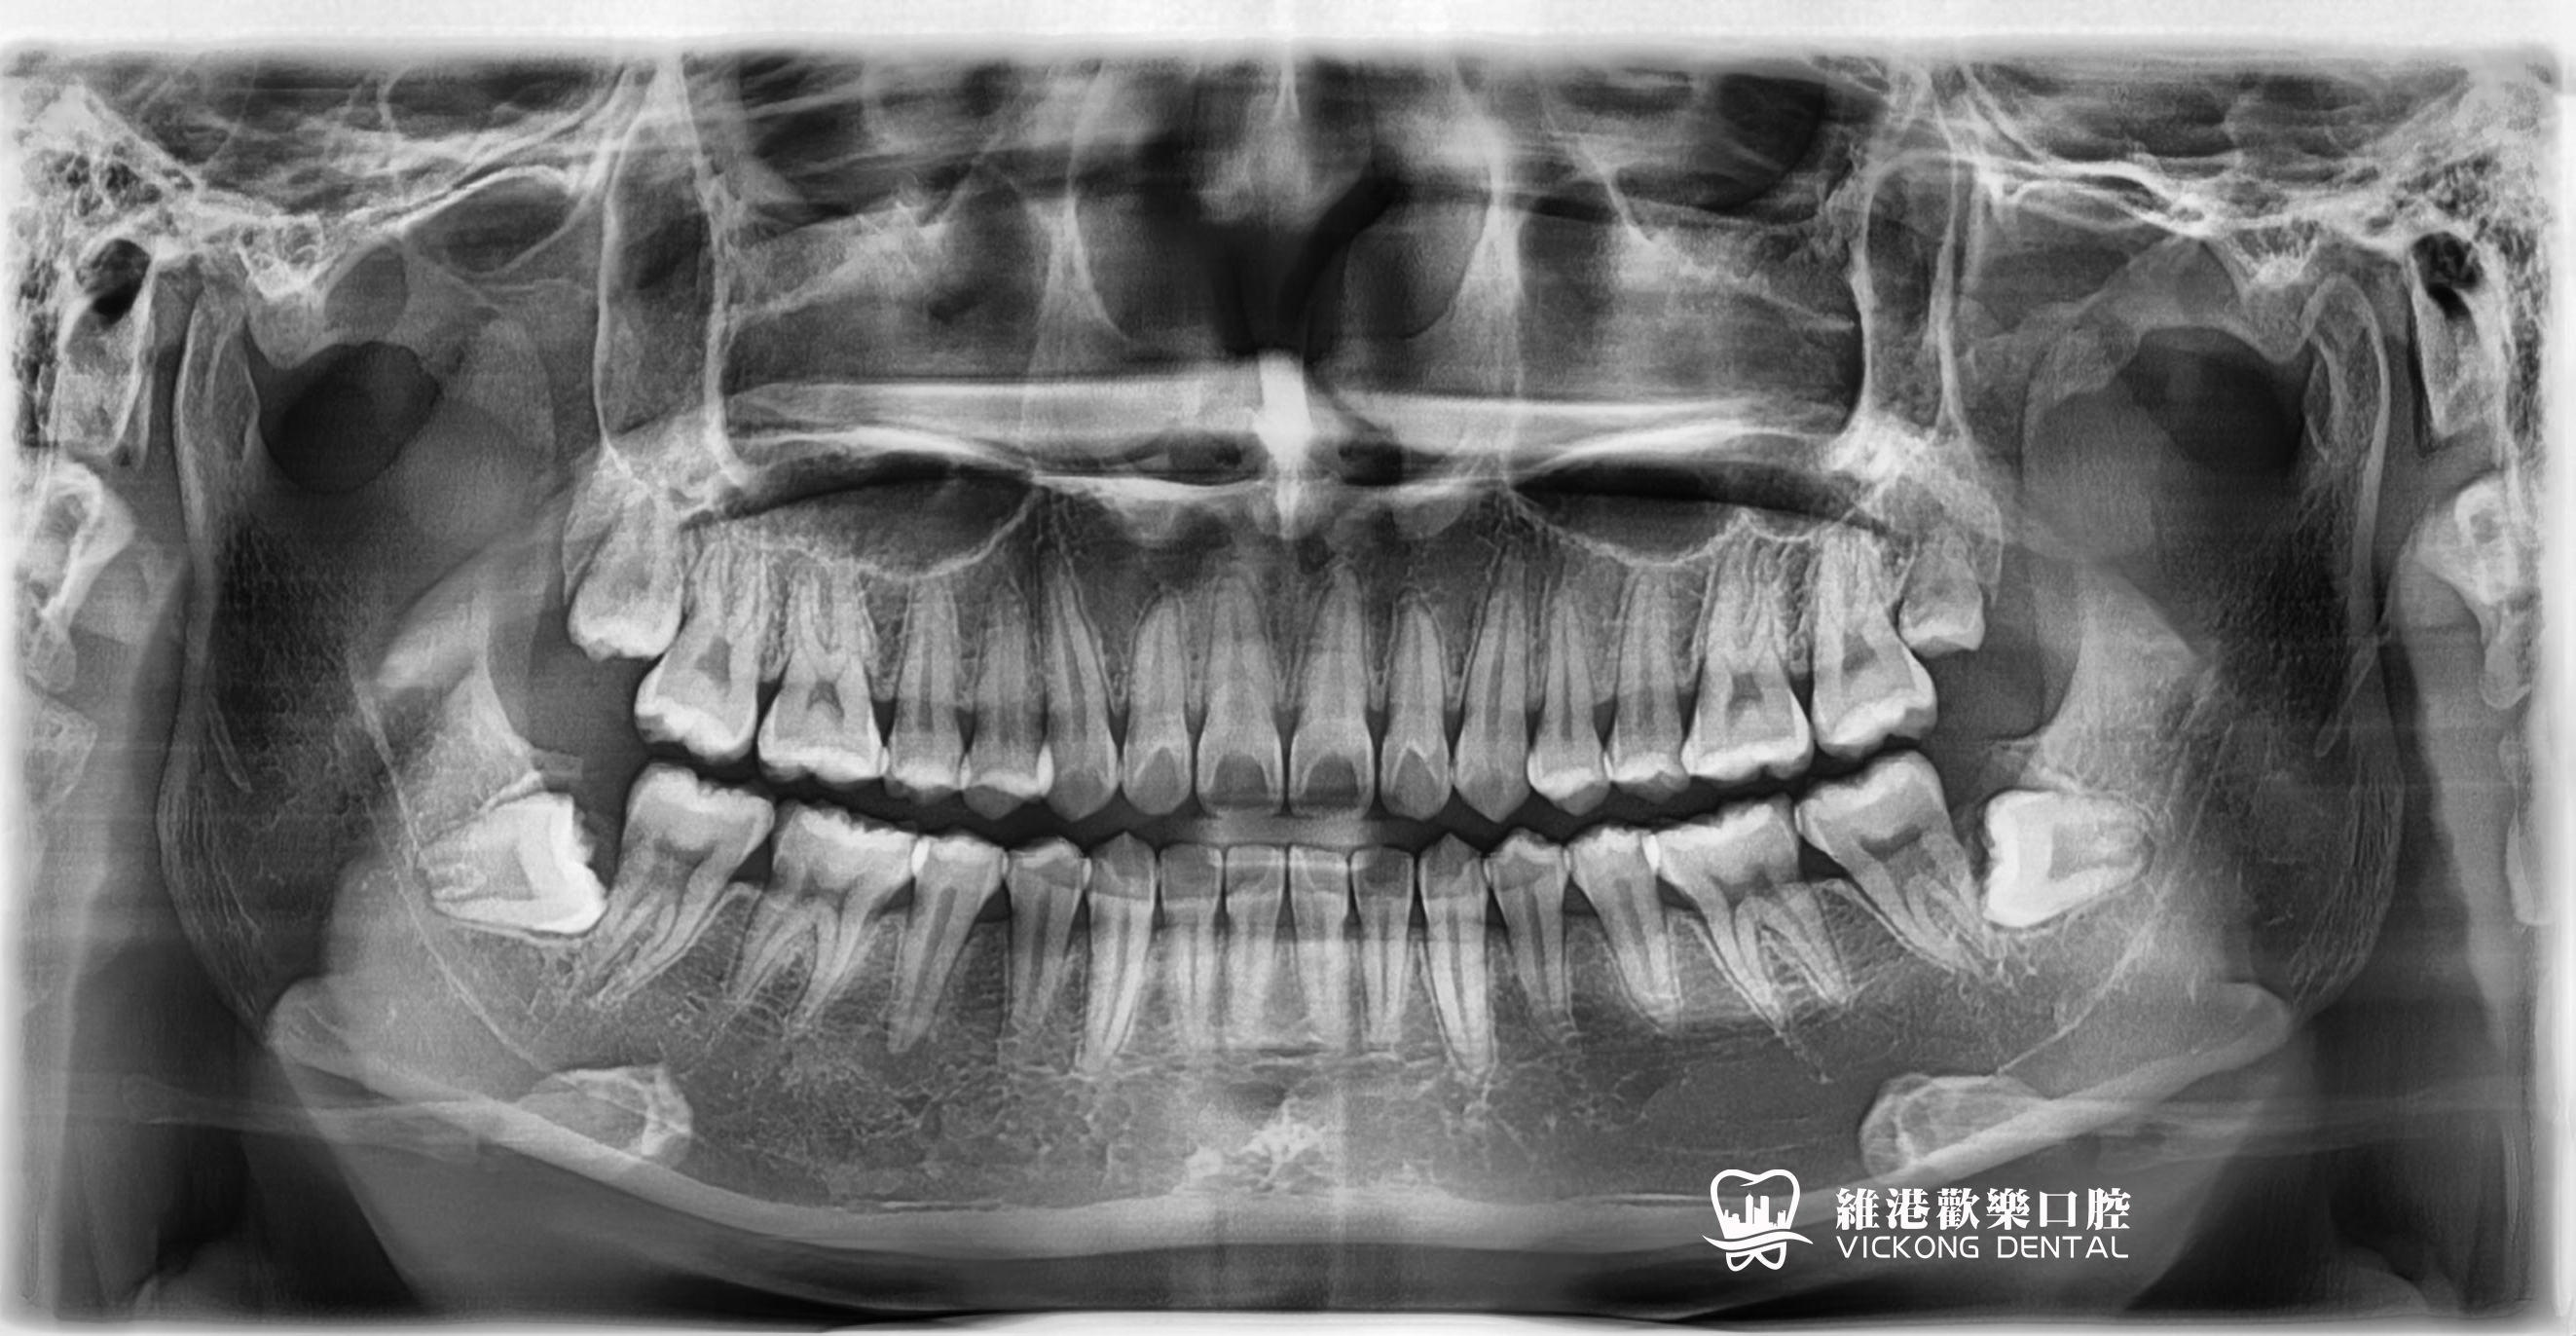

案例分享:

拔除阻生智慧齒:阻生智慧齒周圍的牙齦常常會發炎,疼痛,嚴重時臉頰可以腫脹,張口困難,甚至全身發熱,頜下淋巴結腫大。阻生牙常常還會引起鄰牙齲壞,鬆動,牙槽骨吸收等症狀。